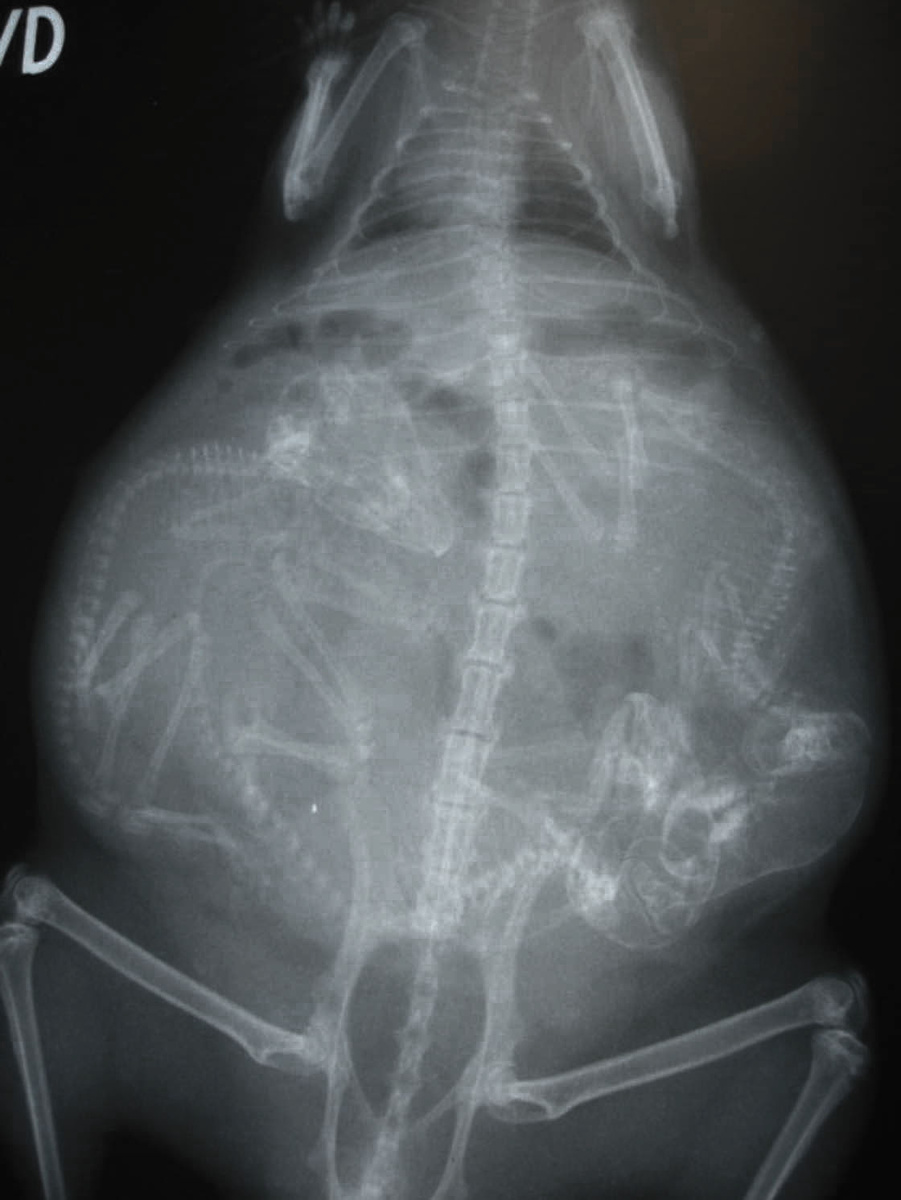

7.Собака.

Как и люди, собаки вынашивают своих детёнышей в течение трех триместров по 21 дню каждый.